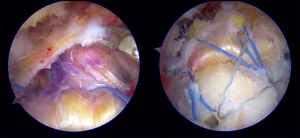

For SCR, a direct lateral portal was used as the main viewing portal in a standard beach chair position. A standard diagnostic arthroscopy was performed to confirm the status of the articular cartilage and the subscapularis integrity. The subscapularis integrity is important as the presence of it will associated with the clinical outcomes and complication rates following SCR (47). More importantly, detailed assessment of the rotator cuff tears should be performed after meticulous removal of the degenerative subacromial bursal tissue and articular release (Figure 2). To assess the repairability of the tendon, a retriever was usually used to grasp the tendon edge and reduce it to the footprint through an anterolateral portal. The distance between the expected anterior glenoid anchor and the expected anterior medial row humeral anchor was measured using a probe (mediolateral graft length) (23). The distance between the expected anterior to the posterior glenoid and medial humeral anchor was also measured (anteroposterior graft length). A radiofrequency ablation device was used to mark the location for the anchor. The graft harvesting and preparation are performed once the tear has been decided to be irreducible.

After the glenoid anchoring, the next step is perhaps the most challenging step in performing SCR, namely, graft shuttling. The lateral portal was extended to 2–2.5 cm to allow for graft shuttling with a push and pull maneuver under direct arthroscopic guidance. At this point, the posterior portal serves as the viewing portal. All sutures from the glenoid anchors were retrieved to the main working portal (direct lateral portal). Using a free needle, the graft was sutured with the glenoid anchor suture limbs externally. We do not advocate the use of an antegrade suture passer for suturing because of the risk of a broken needle tip owing to graft stiffness (from mesh reinforcement) and thickness, which was supported by a previous study (49). The graft is shuttled in by pushing the graft with a Kelly clamp by the surgeon and gently pulling the glenoid anchor suture limb by the assistant under direct arthroscopic guidance. We control the orientation of the graft by making sure that the marked side (bursal side) and the glenoid suture limb are always visible. All sutures were tied when the graft was fully seated on the glenoid. A cross-linked tie between the sutures from the 12 o’clock anchor to the 10 and 2 o’clock anchors was routinely performed.